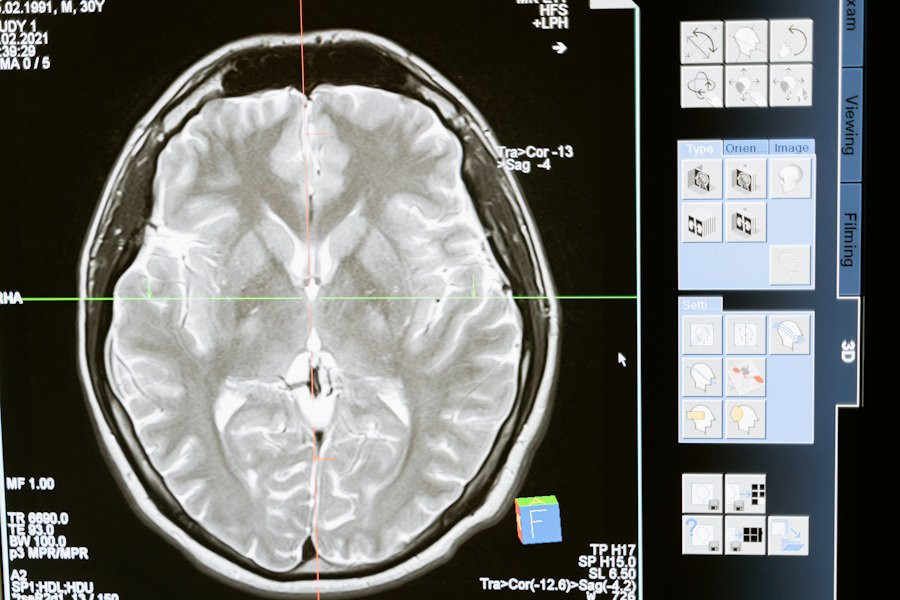

Ранее ученые использовали функциональную магнитно-резонансную томографию (фМРТ), чтобы определить области мозга, связанные с языковой обработкой. Однако фМРТ, которая измеряет изменения кровотока, не обладает достаточной разрешающей способностью для выявления работы небольших популяций нейронов. Это ограничивало возможность точно определить, какие функции выполняют отдельные группы нейронов.

Новое исследование MIT открыло важные детали этой сложной сети. Используя методику записи электрической активности непосредственно из мозга, ученые обнаружили, что различные кластеры нейронов обрабатывают информацию в так называемых «временных окнах». Эти окна варьируются по длине от одного слова до шести слов.